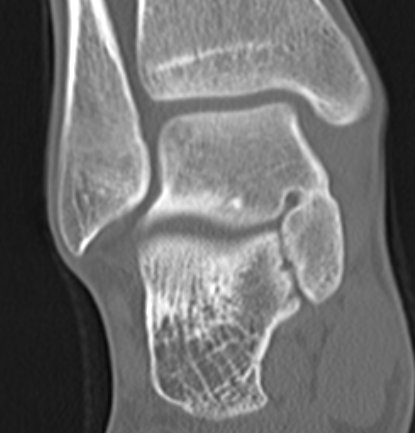

CT

TC coalition middle facet

Complete synostosis of the medial TC joint with OA of the posterior subtalar joint